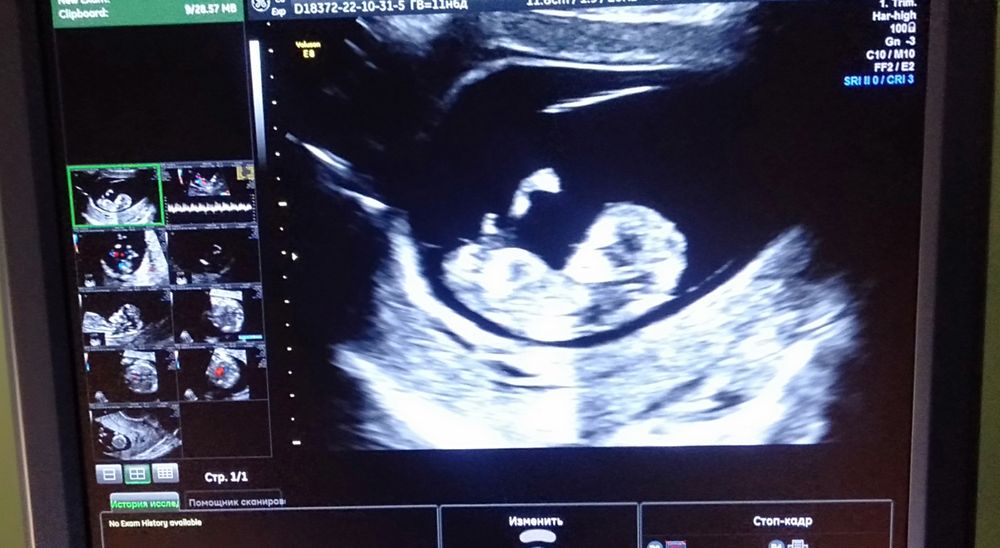

Узист которая не стала предпологать пол моего малыша разрешила мне сфотографировать его с экрана монитора) вот теперь гадаю я, это половой бугорок торчит или ещё нет.Срок на момент УЗИ 11 недель,пять дней. Половой бугорок она не увидела,сказала что на этом сроке мальчиков лучше видно,а тут пока всё плоско. Даже предположений нет. Вот просто интересно ваше мнение) полового бугорка на фото нет.

Хахах) это же какой должен быть большой бугорок то?) 😄Ножка это) ждите следующее УЗИ или сходите от себя на платное) я так делала, если в чем-то сомневалась. Например я так отслеживала обвитие пуповиной. Да, там все показания смотрят снова, зато спокойно, когда удостовериваешься хоть в 10000 раз

Это ножка, даже две на этом кадре. Одна закрывает половой бугорок. Не может он быть такой большой))

Если на фото полового бугорка нет, и Вы это сами понимаете, то смысл спрашивать?))